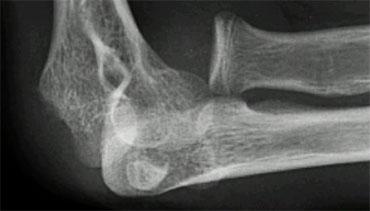

Supracondylar fractures. In A the anterior humeral line passes through the anterior third of the capitellum and in B even more anteriorly. Notice positive posterior fat pad sign in both cases

Gãy xương trên lồi cầu (2)

Nếu chỉ có di lệch tối thiểu hoặc không có di lệch, các gãy xương này có thể ẩn trên phim X-quang.

Dấu hiệu duy nhất sẽ là dấu hiệu đệm mỡ dương tính.

Thường có một số di lệch và đường cánh tay trước sẽ không đi qua trung tâm của chỏm con mà đi qua một phần ba trước hoặc thậm chí phía trước chỏm con (hình).